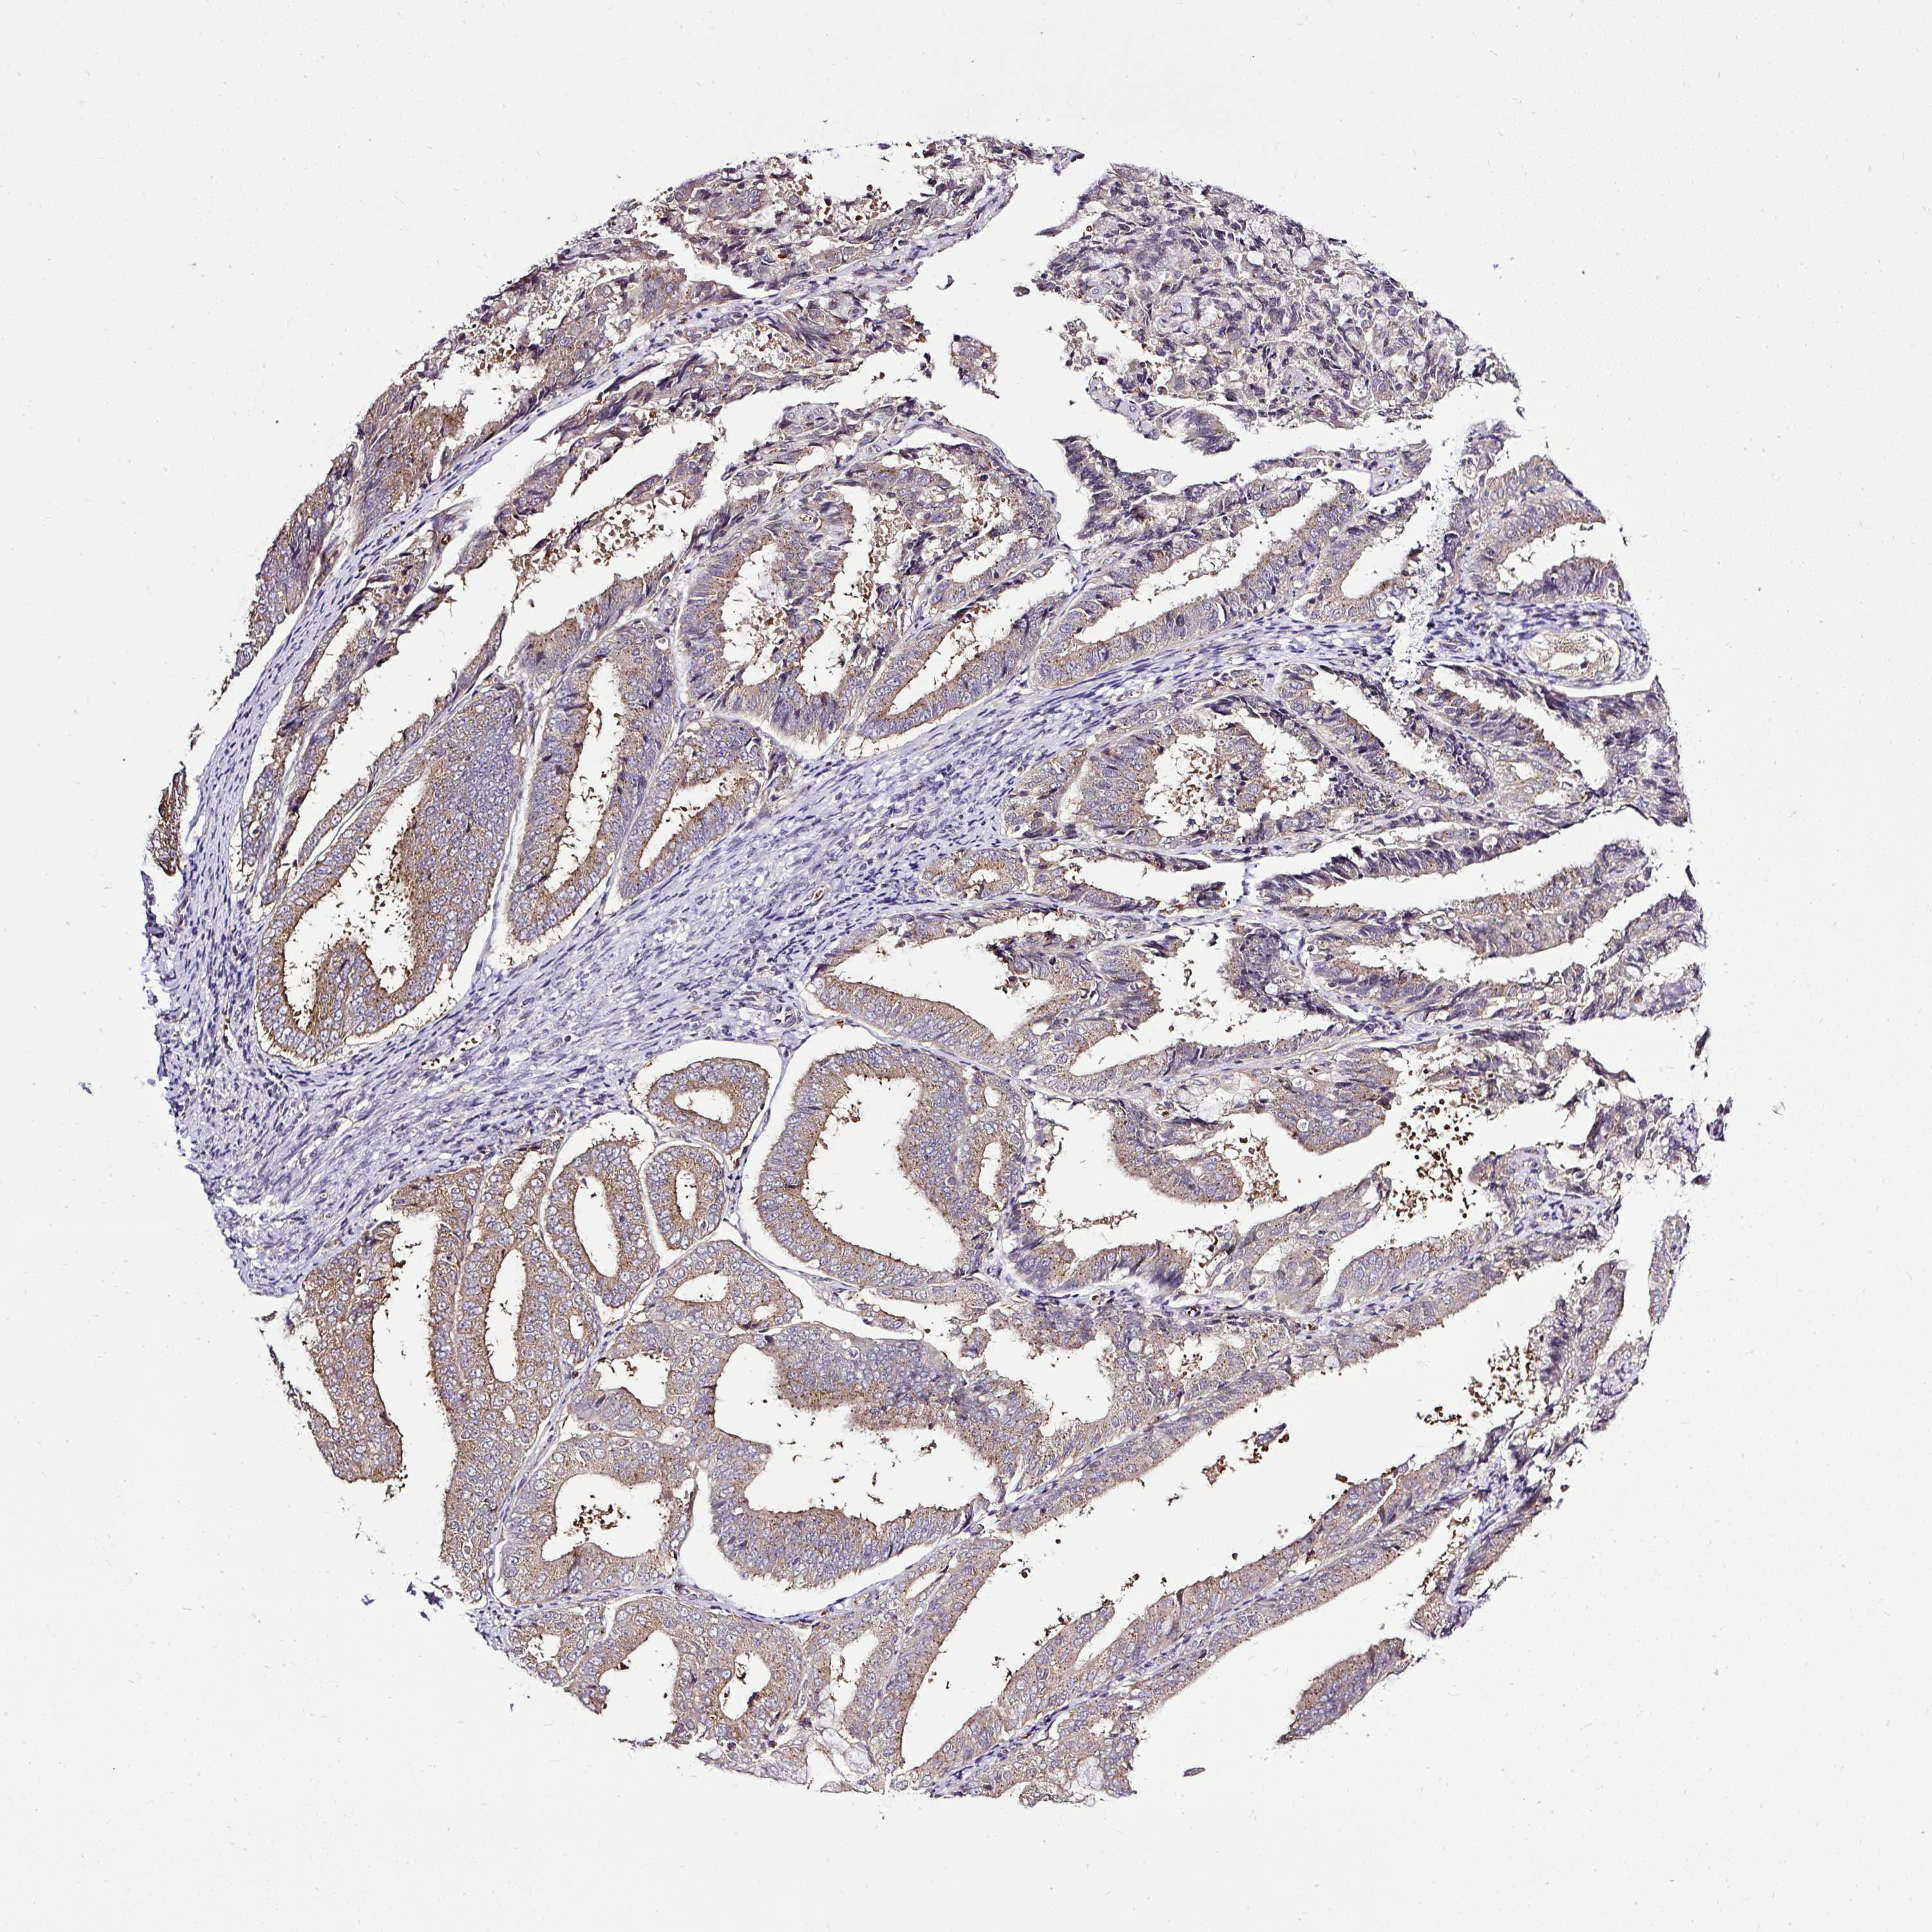

ENDOMETRIAL CANCER - Protein expressioni

A mouse-over function shows sample information and annotation data. Click on an image to view it in a full screen mode. Samples can be filtered based on level of antibody staining by selecting one or several of the following categories: high, medium, low and not detected. The assay and annotation is described here.

Note that samples used for immunohistochemistry by the Human Protein Atlas do not correspond to samples in the TCGA dataset.

Antibody stainingi

Antibody staining in the annotated cell types in the current human tissue is reported as not detected, low, medium, or high, based on conventional immunohistochemistry profiling in selected tissues. This score is based on the combination of the staining intensity and fraction of stained cells.

Each image is clickable and will lead to virtual microscopy that enables deeper exploration of all samples and also displays staining intensity scores, fraction scores and subcellular localization as well as patient and tissue information for each sample.

Antibody HPA029449

Antibody CAB055509

Staining

High

Medium

Low

Not detected

Intensity

Strong

Moderate

Weak

Negative

Quantity

>75%

75%-25%

<25%

None

Location

Nuclear

Cytoplasmic/membranous

Cytoplasmic/membranous,nuclear

Adenocarcinoma, metastatic, NOS